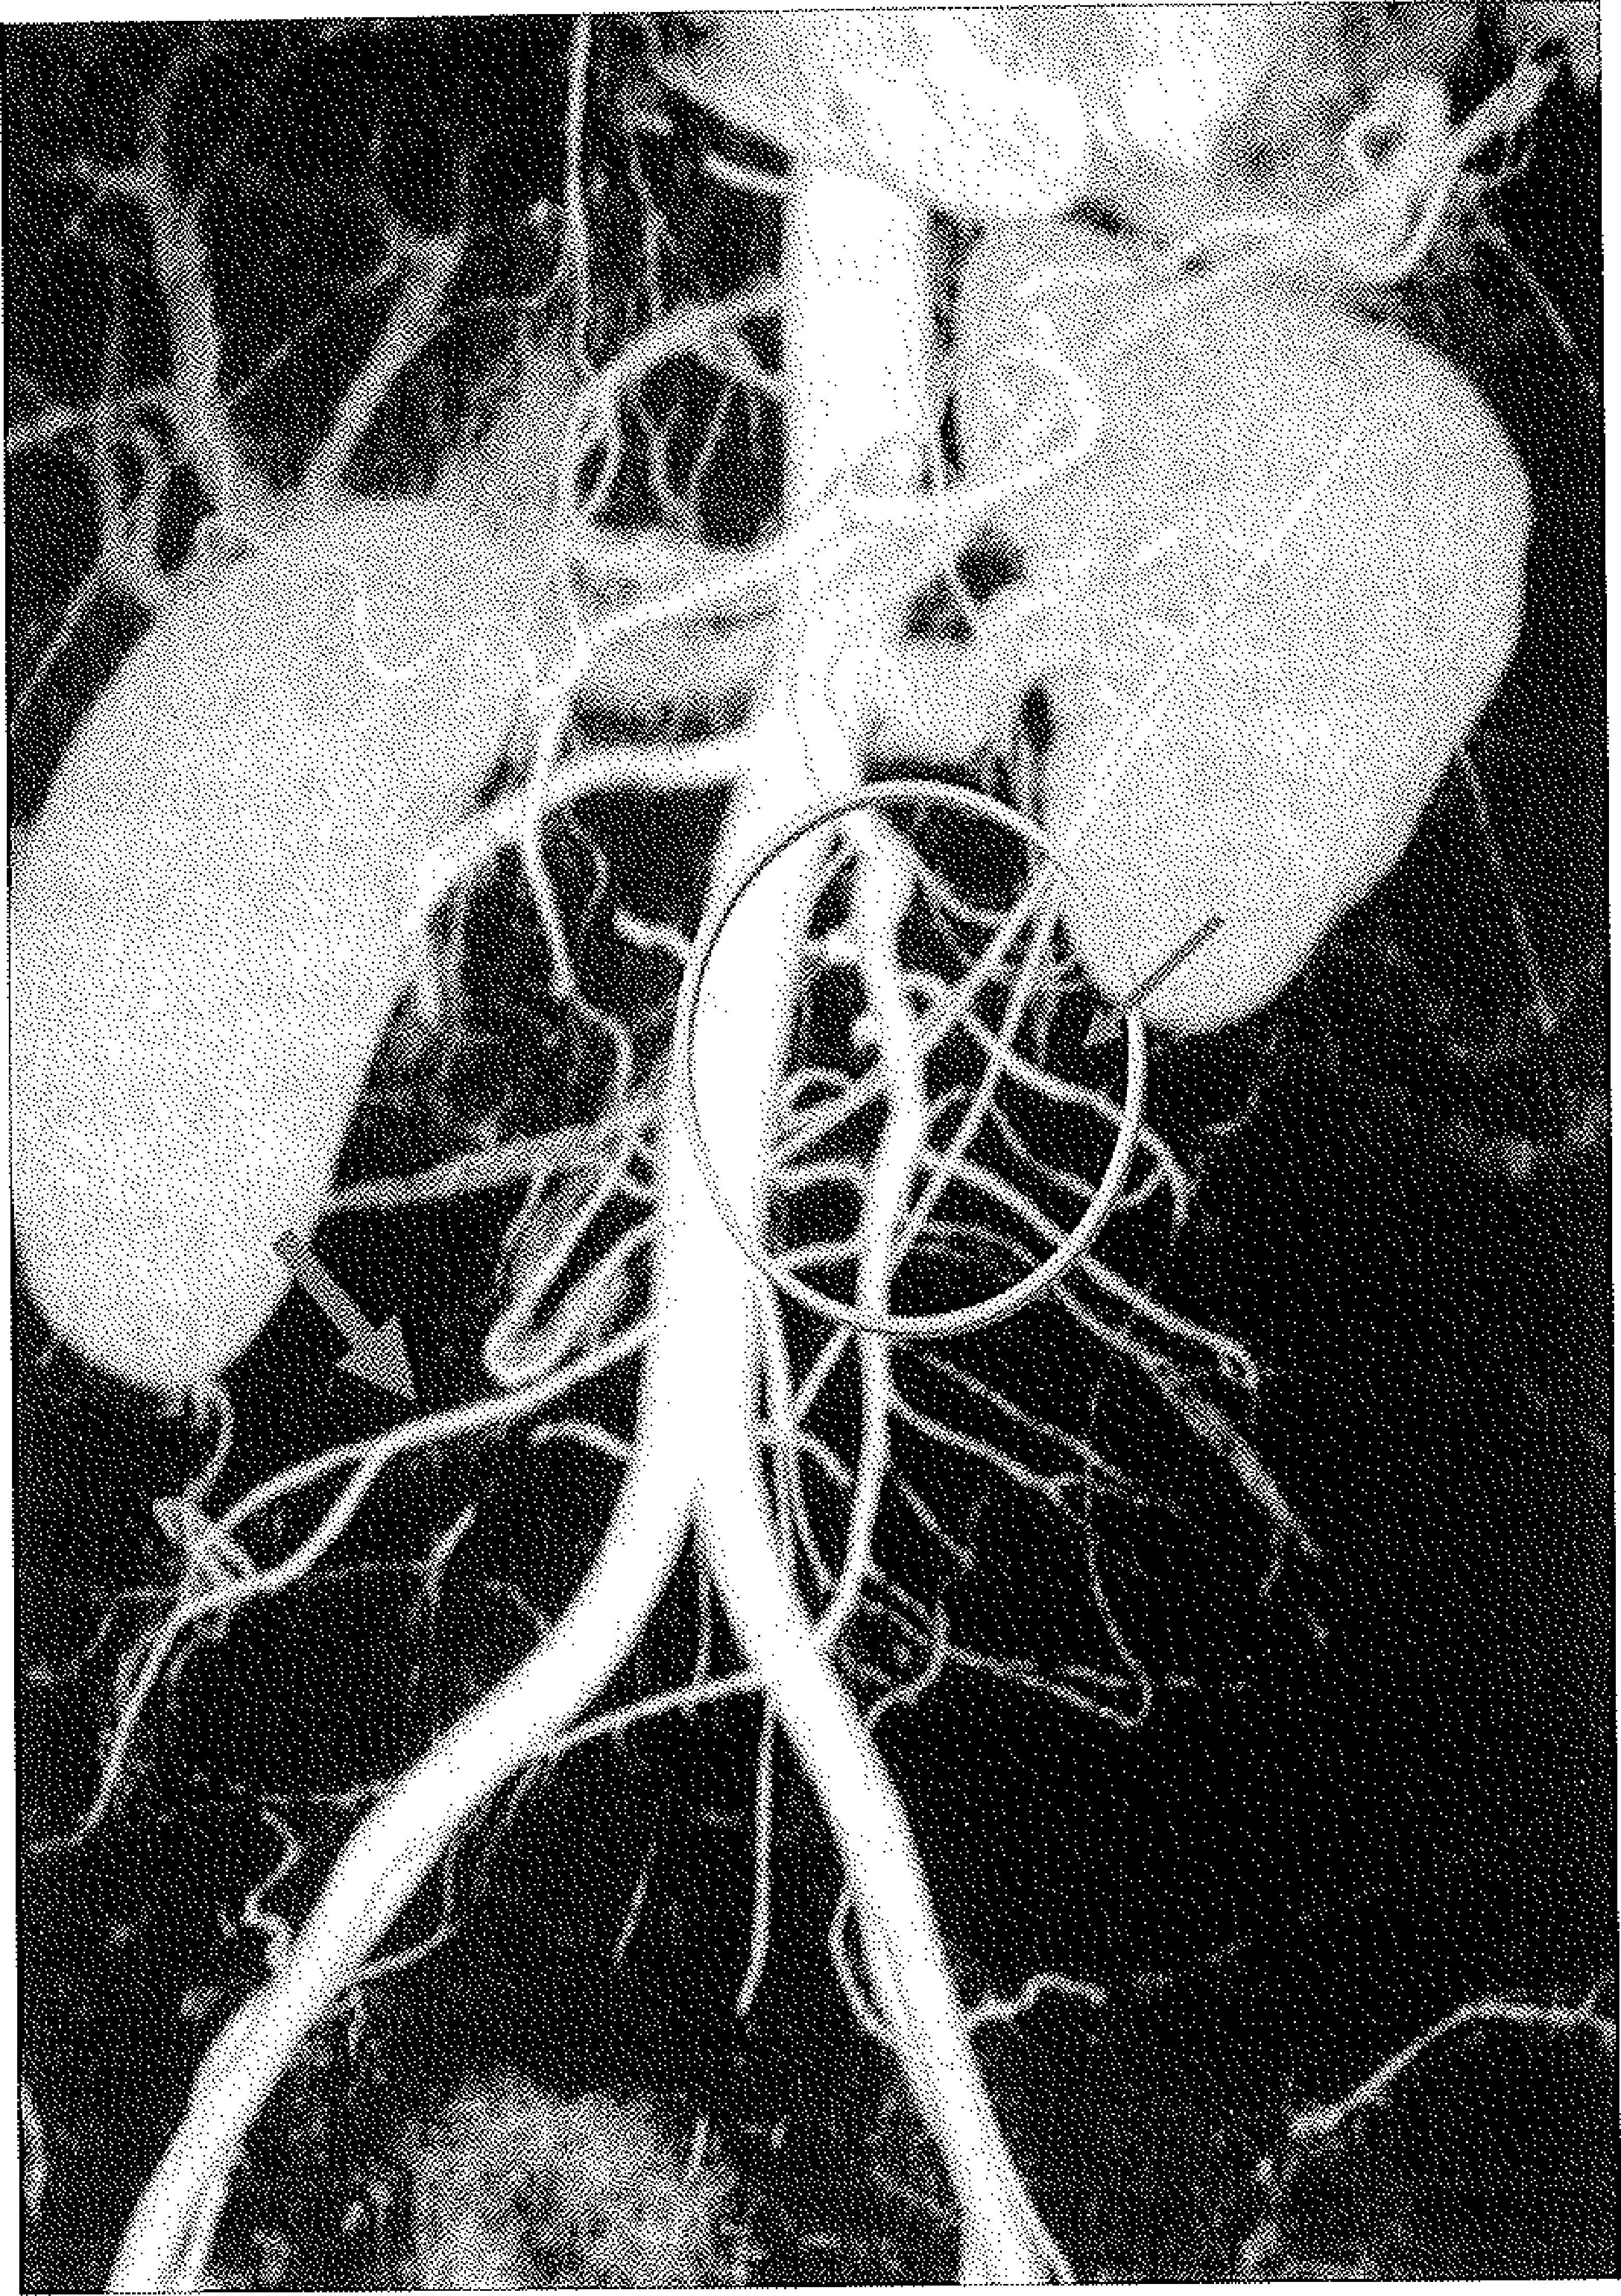

Caso clínicoMujer de 27 años sin antecedentes de interés, que acude a urgencias en dos ocasiones por dolor abdominal de tipo cólico de aparición espontánea, no relacionado con la ingesta, de cuatro semanas de evolución. En la primera visita, la exploración abdominal es anodina y se realiza una analítica, que resulta normal. La segunda vez que acude se realiza una ecografía donde se evidencia la existencia de un aneurisma en la arteria mesentérica superior, sin otros hallazgos destacables. Se realiza una angiotomografía (Fig. 1) y una arteriografía selectiva (Fig. 2), donde se observa el aneurisma en el tercio medio de la arteria y con dos ramas yeyunales de calibre importante por la izquierda y las arterias cólica derecha e ileocólica por la derecha. Una TAC torácica, otra craneal y un eco-Doppler carotídeo descartan la existencia de lesiones vasculares asociadas. Así mismo, se descarta la existencia de cualquier tipo de infección en los últimos nueve meses, lo que, en principio, elimina la posibilidad de que el aneurisma fuera de origen infeccioso. Durante los estudios preoperatorios realizados de forma ambulatoria, la paciente presenta nuevos episodios de dolor abdominal similar a los anteriores, refiriendo que eran más frecuentes en las últimas semanas. Al planificar el tratamiento se descarta la exclusión del aneurisma mediante endoprótesis dado que habría que ocluir las ramas yeyunales y posiblemente la rama ileocólica, con el consiguiente riesgo de isquemia mesentérica. En la intervención mediante laparotomía media supraumbilical, y tras tracción del mesocolon transverso, se localiza fácilmente la masa pulsátil en el mesenterio, comenzando por aquí la disección. Se realiza control de la arteria mesentérica superior a unos 4-5cm de su salida de la aorta y resección del aneurisma e interposición de un injerto de vena safena interna, con reimplantación de una de las arterias yeyunales por su calibre, preservando distalmente la otra yeyunal y la rama ileocólica (Fig. 3). La paciente es dada de alta a los cinco días de la intervención sin que existan complicaciones durante el postoperatorio. Los cultivos de la muestra son negativos. La anatomía patológica informa de desorganización fibromuscular de la media, adventicia fibrosa con infiltrado inflamatorio crónico compatible con displasia fibromuscular. A los seis meses, el injerto sigue permeable y la paciente no ha vuelto a sufrir dolor abdominal.